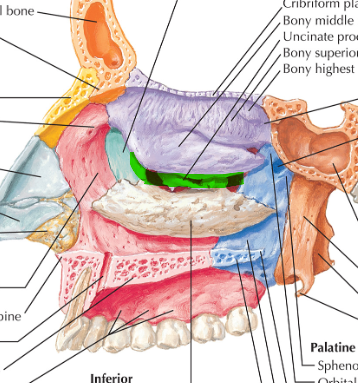

Hueso Etmoides

Parte anterior y media de la base del cráneo

Forma parte de las fosas nasales, cavidades orbitarias y craneal

Lámina vertical del etmoides

Lámina perpendicular del etmoides

Forma parte del tabique de separación de ambas fosas nasales (septum/tabique nasal)

Apófisis crista galli por arriba de la lámina horizontal

Apófisis crista galli

Triangular, borde anterior bajo articula con el hueso frontal y completan el agujero ciego(foramen cecum) entre surcos

Lámina cribosa del etmoides

Lados se articulan con el frontal

Forma parte del piso de la fosa craneal anterior

Perforada por múltiples orificios, por eso el nombre de cribiforme

Dos apófisis alares que articulan con el frontal, creando el foramen cecum

Cornete nasal superior

Cornete nasal medio

Laberintos Etmoidales

Forma parte de la pared lateral de las fosas nasales

Lámina papirácea en cara lateral

Lámina papirácea del etmoides

Cara orbitaria del etmoides

Lámina delgada y lisa, frágil como un PAPIRO!

Forma una gran parte de la pared medial de la órbita